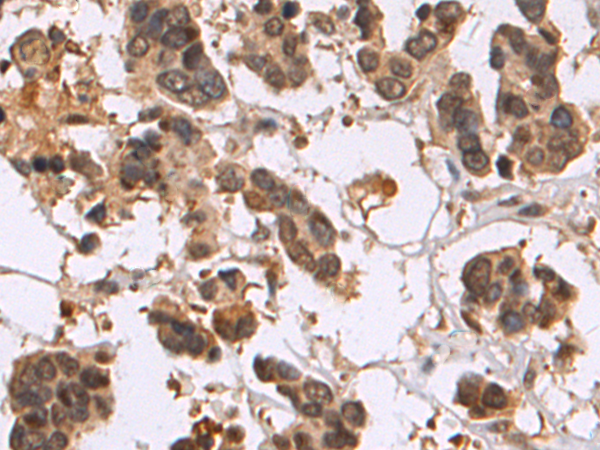

分类: 科研抗体货号: P10655别名: RAY, H-ray, RAB1C应用: IHC反应种属: Human, Mouse, Rat

-